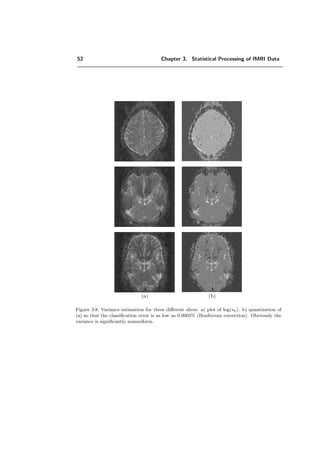

3.3 fMRI applications . . . . . . . . . . . . . . . . . . . . . . . . . . . . . . . . 47

3.3.1 Noise in fMRI data . . . . . . . . . . . . . . . . . . . . . . . . . . . 47

3.3.2 Deterministic model . . . . . . . . . . . . . . . . . . . . . . . . . . . 53

3.3.3 Hypothesis testing for activation . . . . . . . . . . . . . . . . . . . . 54